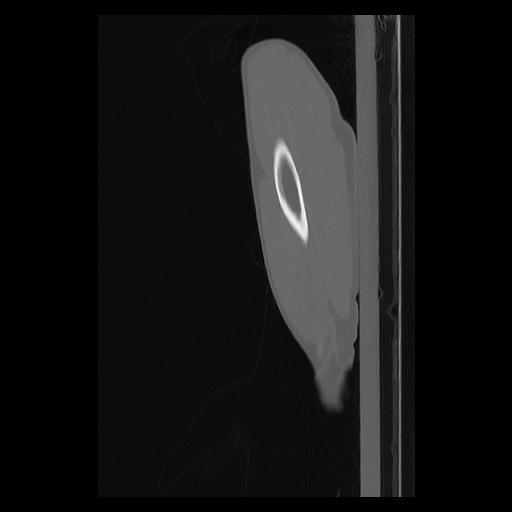

33 PULMON,CE,Sagittal,3.000,PULMON,Sagittal,